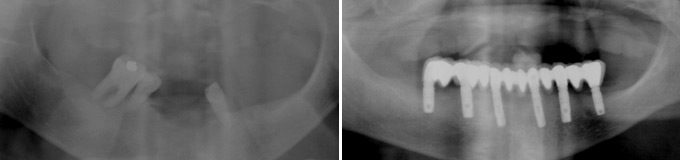

Toutes les dents du bas sont perdues, on fait les extractions, la mise en place des implants et en même temps la mise en place du bridge FIXE provisoire : pas d’appareil amovible à supporter!

Les trois dents du bas qui tiennent mon appareil sont perdues. Un bridge fixe complet sera réalisé pour supprimer l’appareil inférieur.

Dans ce cas, la prothèse amovible inférieure est supprimée, remplacée par un bridge fixe de 10 dents.